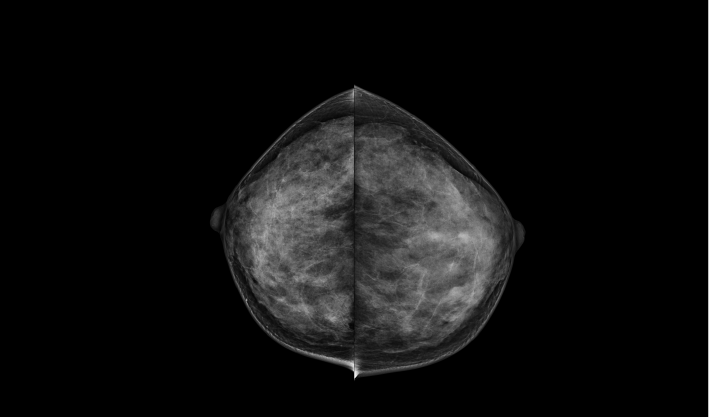

頭尾位(CC位) 內外斜位(MLO位) 補充體位(根據需求)

一鍵式視圖切換